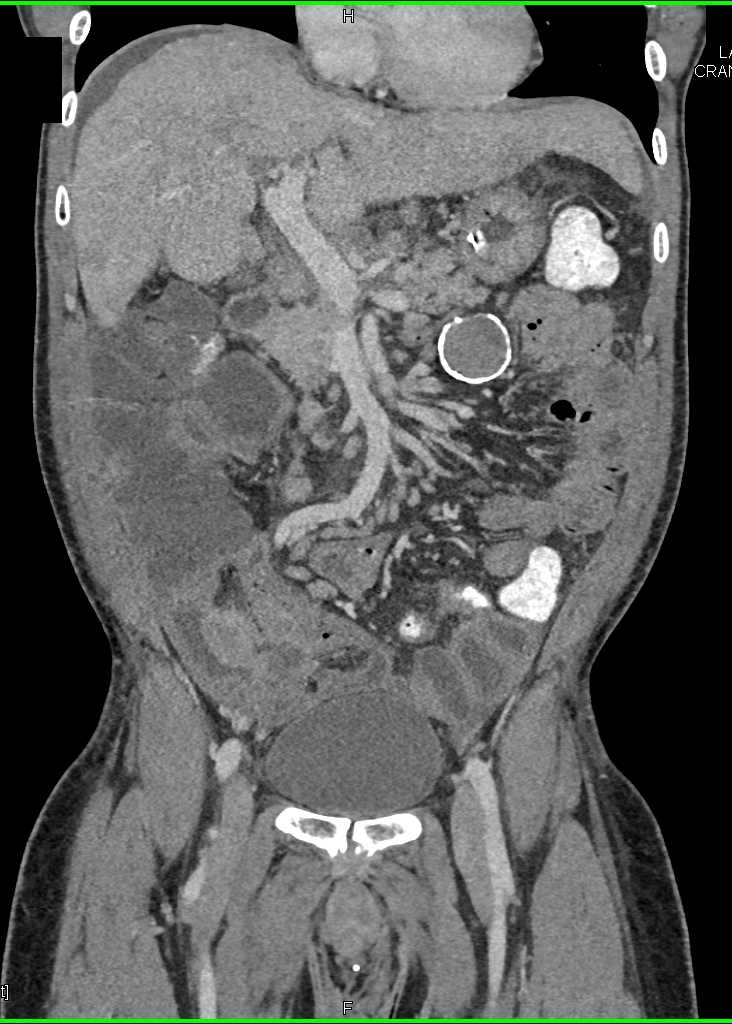

Small Bowel Carcinoma with Carcinomatosis